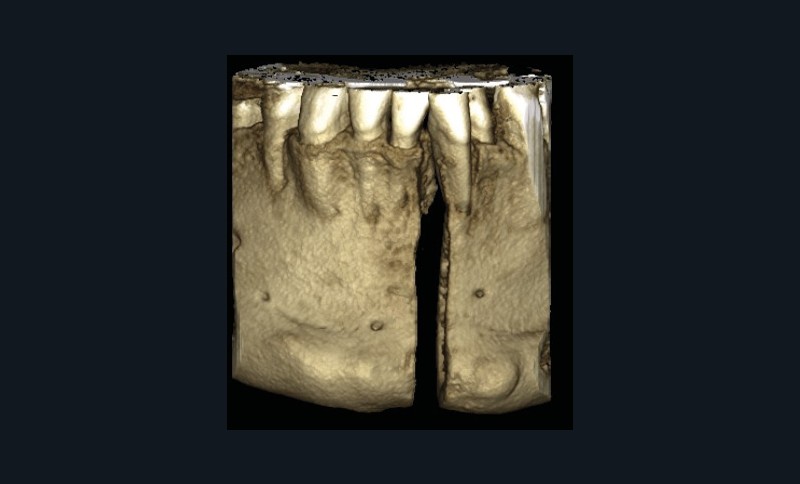

Le Dr Christophe Dunglas développera ensuite l’intérêt du cone beam lors de la mise en place des canines incluses difficiles. En effet, la préparation d’ancrages adéquats et de gestes chirurgicaux a minima préviendra l’apparition de résorptions radiculaires et de lésions parodontales.

Cette imagerie moderne montrera encore toute sa pertinence, au cours de la présentation du Dr Arnaud Lafon qui nous fera partager son expérience des transplantations dentaires. Longtemps considérée comme le « marronnier » de l’orthodontie, cette technique bénéficie maintenant d’un protocole bien établi et se révèle être une alternative très intéressante à l’implantologie, notamment chez les adolescents ou en cas de budget réduit. Solution immédiate, elle est parfaite lors d’avulsions des premières molaires mandibulaires cariées dans un protocole ortho-chirurgical. Plus besoin d’attendre la mise en place des troisièmes molaires pour envisager le geste de propulsion mandibulaire !